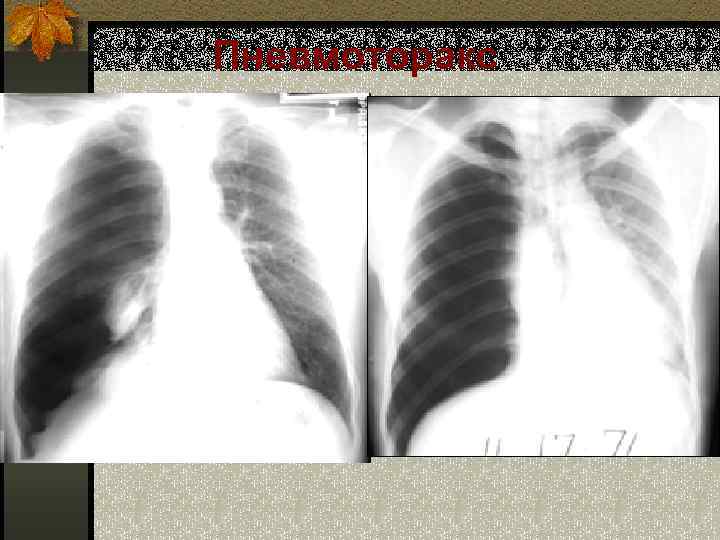

Пневмоторакс